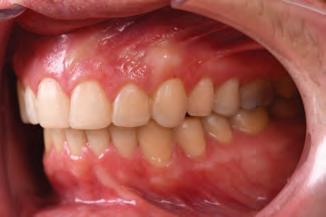

A 31-year-old woman presented with cosmetic concerns regarding her smile and requested a conservative enhancement. After clinical and radiographic analysis, digital 35mm photographs were taken and reviewed by the restorative clinician, technician, and surgeon (Fig 1). A digital impression was taken of the maxillary and mandibular arches using an intraoral scanner (Trios 3, 3Shape; Fig 2), and a smile design was developed with NemoSmile Design 3D software (Nemotec; Fig 3a). This allows for a facially driven smile frame to be created using reference lines of facial and smile proportions and natural teeth shapes and textures from the digital library (Fig 3b).

Fig 1 Preoperative clinical views of a 31-year-old woman presenting with diastemas and limited tooth visibility. (top) Portrait. (center row) Intraoral views. (bottom row) Smile.

4b). This matrix was used to create an intraoral motivational mock-up with bis-acryl composite (Luxatemp Ultra, DMG). This additive mock-up provides the interdisciplinary team with an intraoral translation for evaluation (Fig 5). Upon evaluation of the digital smile frame and the clinical translation, it was determined that multiple esthetic and restorative requirements were necessary for an optimal biologic framework, and the interdisciplinary team determined the best sequence for these procedures. The patient was presented with the interdisciplinary treatment possibilities that included restoring the maxillary anterior teeth and premolars with a minimally

invasive preparationless procedure or with less conservative veneer preparations. The restorative materials discussed included injectable resin composites and ceramic (ie, feldspathic, pressable, machinable). For an optimal biologic framework and health, it was determined that connective tissue grafting would be necessary for treatment of the recessiontype defects on the maxillary left central and lateral incisors, canine, and premolars. The patient opted for the conservative preparationless composite veneers using the injectable resin technique followed by a connective tissue surgical procedure using the tunneling technique.